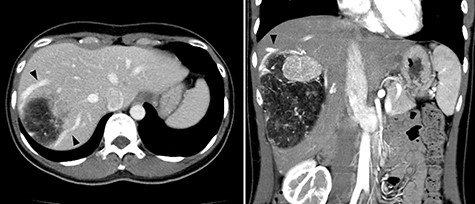

A 45-year-old woman was referred to our hospital with a huge liver tumor, which had been diagnosed as HAML 5 years previously when it was 12 cm in diameter (Fig. 1). Periodic follow-up with ultrasound and magnetic resonance imaging after the initial diagnosis had shown a progressive increase in the size of the tumor, and by the time of referral it measured 20 × 14 cm and had become symptomatic. On admission, enhanced computed tomography revealed a very large, well-defined, mixed-density mass occupying the entire right lobe of the liver (Fig. 2). Angiography showed dilated and tortuous vessel inside the tumor, and a drainage vein from the tumor to the right hepatic vein was visualized in the early phase (Fig. 3).

Abdominal computed tomography (CT) 5 years before referral to our hospital; enhanced CT revealed mixed density tumor measuring 12 × 10 cm in the right lobe of the liver; a peritumoral early drainage vein around the tumor (arrow heads) was visualized.